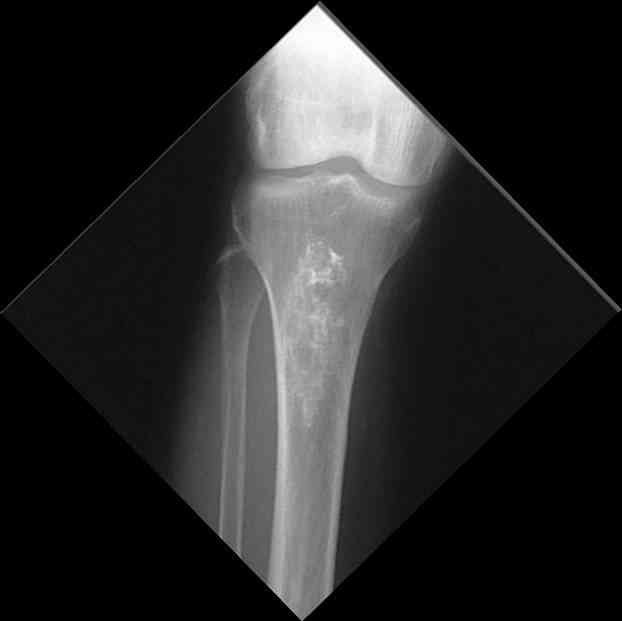

Изменения структуры костей у Вашего пациента больше похожи на полиоссальную форму фиброзной дисплазии или болезнь Педжета, возможены также инфаркты костного мозга б.берцовых костей. К сожалению, качество снимка не очень хорошее, непонятно, сохранен ли кортикальный слой б.берцовых костей по передней поверхности.

Для примера привожу случай из архива американской ассоциации рентгенологов (ACR) - развитие злокачественной фиброзной гистиоцитомы на левой б.берцовой кости у пациента с множественными инфарктами костного мозга (рис 4,5 - левая, рис 6 - правая)